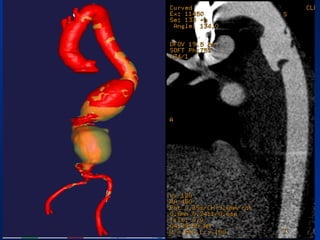

• Preoperative CT 1mm imaging to include pelvisPreoperative CT 1mm imaging to include pelvis